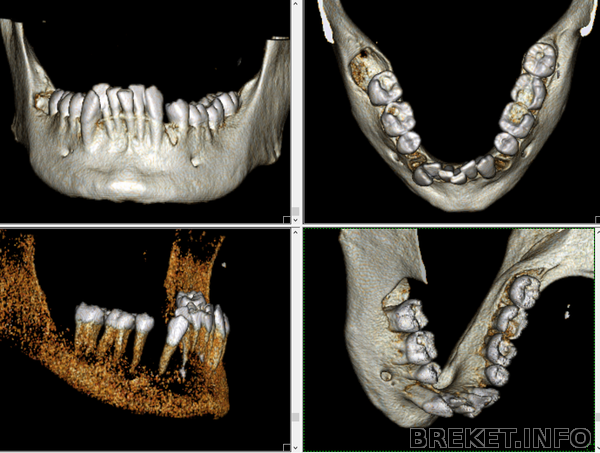

Скриншоты томографии нижней челюсти: